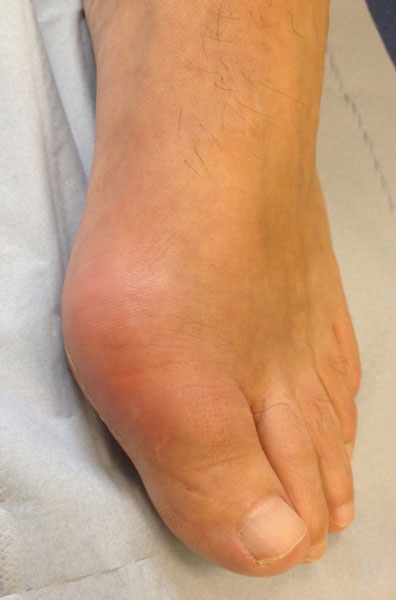

Although radiographic changes are usually a late feature, occasionally they may be seen at presentation, see figure 1. The most common presentation is a gout flare, characterised by acute onset of one, or occasionally more, hot, red, swollen joints which are extremely painful and exquisitely tender. Flares reach a peak in just 12-24 hours. Although any joint can be affected, most flares affect joints in the feet, knees, hands or elbows. Involvement of the first metatarso-phalangeal joint, termed podagra (seizing the foot), is very characteristic, see figure 2.

A less common presentation is insidious onset of chronic usage related joint pain, especially in joints already affected by osteoarthritis (e.g. finger interphalangeal joints with nodal osteoarthritis). Subcutaneous tophi can also be the presentation, especially in older people, see figure 3.